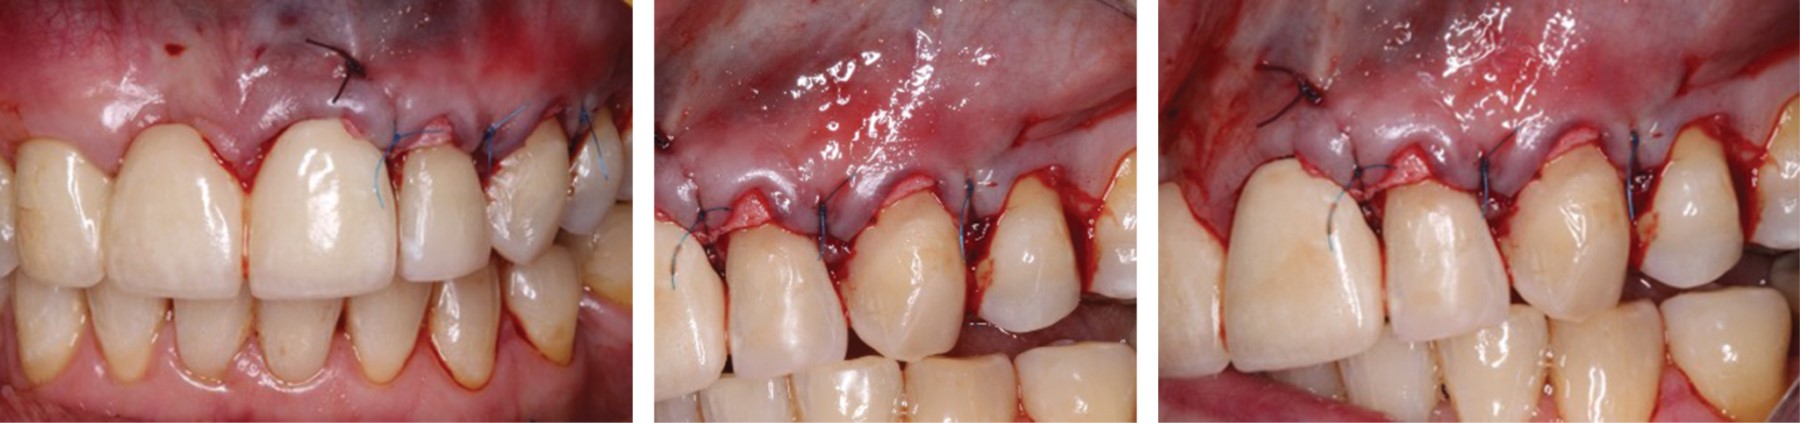

Figure 3